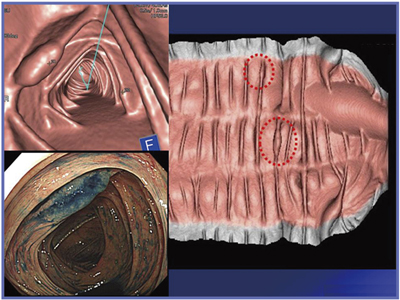

一次チェックにあたっては,使用しているワークステーション(WS)の表示画像の特徴を理解することが,最も重要である。当院で用いているWS(ziostation2:ザイオソフト社製)の大きな特徴は,大腸を開いて伸ばしたVGP像である(図3)。歪みはあるが,大腸全体の粘膜面に異常がないかどうかを評価するには,非常に適している。

一次チェックでは,まず大腸を抽出したVR像で,壁に変化があるかどうかを観察する。次に,VGP像で全粘膜面をチェックし,変化が認められればVE+MPR像で腸管の内外を確認する。その後,VE像で全体を見ていく。

最終的には,病変が疑われる画像を提供するが,見る角度をマウスで操作すると,襞が引きつったように描出されるなど,存在診断だけでなく,質的診断も可能ではないかと考えている。

図3 VGP(仮想切除標本展開像)2体位比較評価(ザイオソフト社製ziostation2)

2012年1月よりCTC撮影加算が認められるようになったことで,今後CTCは急速に普及していくことが予想される。1日に数例のCTCを行う施設では,CT本体コンソールのWSで十分評価可能である。Aquilion CXLのコンソールWSにおけるコロンビューイングソフトウエアを用いたlaterally spreading tumor(LST)の展開像でも,襞の上に大小2つの病変がはっきり描出されているのがわかる(図4)。VE像,MPR像も,コンソール上で十分に評価することができる。

図4 Aquilion CXLのコンソールWSでの画像評価

襞の上に病変(○)が認められる。